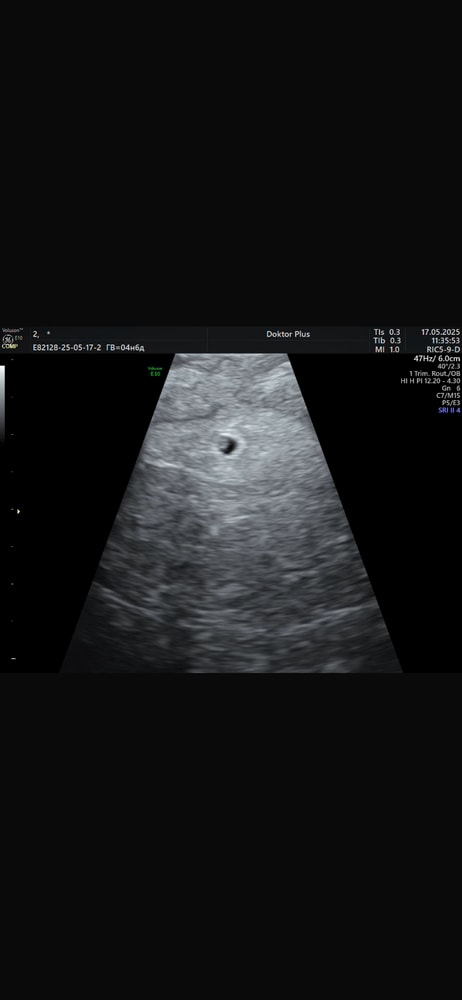

Леся, я не знаю какой у меня точно срок … последние месячные 31 марта начались, цикл у меня 30-31 день , далее задержка. 3 мая тест отрицательный (уже в задержку) , 15 мая тест положительный и хгч 80 … врачи толком ничего не говорят , ставят срок пока по месячным а это на данный момент почти 8 недель ! Но такого не может быть. Сказали будут по ктр срок считать

Леся, я в больнице лежала где мне отслеживали хгч и делали узи раз в два дня для исключения внематочной … зачем мне сейчас пытаться доказать что это что то не нормальное когда бывают такие ситуации с поздней овуляцией или нестандартным циклом ? у меня плодное яйцо нашли три дня назад и в этот день хгч был 1800, а до этого каждые два дня он удваивался и нормально рос. Потому что у меня срок по факту не 8 недель и овуляция у меня была не на 14 дц как у большинства женщин а гораздо позже. И после появления эмбриона срок будут считать по ктр а не по последним месячным

Марии , я надеюсь 🙏 может аппарат у них еще хреновенький ибо делалось узи в государственной больнице когда привезли с подозрением на внематочную 😲 а теперь еще и задумалась о том что плодное яйцо странной формы …

Марии , там внутри будто бы что то есть , но врач ничего не сказала … Изображение

Не видно эмбриона Ктг на 23 недели